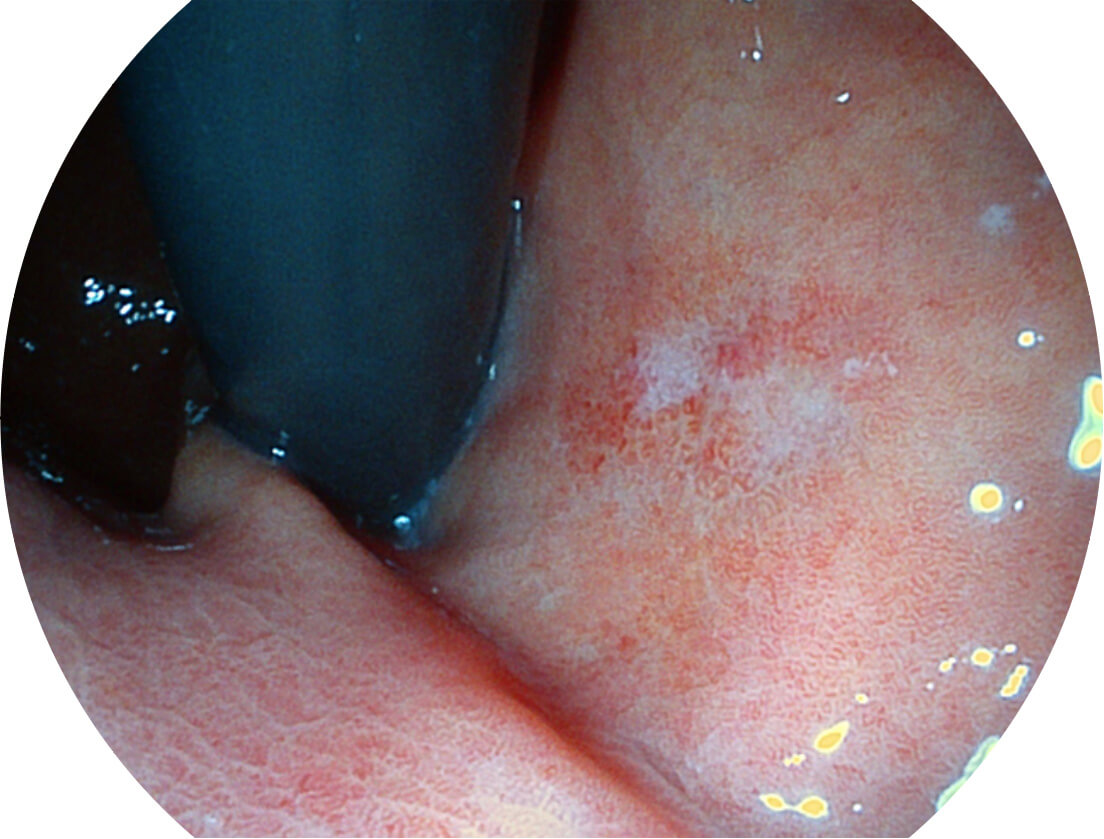

白光图像

VIST图像

Versatile Intelligent Staining Technology, VIST

强调浅层黏膜结构的同时,保证照明亮度和提升浅层微血管与中层血管颜色对比度,病变边界更清晰。